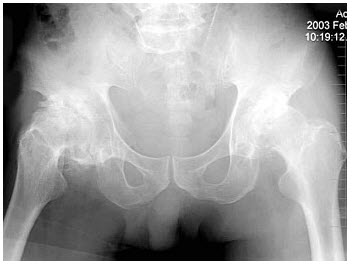

男,60岁,因双髋关节反复疼痛2年余,无明显外伤史,X线摄片如图,最可能的诊断是()

A、双髋关节退行性骨关节病

B、双髋关节创伤性关节炎

C、双髋关节特发性骨关节病

D、双髋关节结核

E、神经性关节炎

男,60岁,因双髋关节反复疼痛2年余,无明显外伤史,X线摄片如图,最可能的诊断是 A.双髋关节退行性骨关节病

B.双髋关节创伤性关节炎

C.双髋关节特发性骨关节病

D.双髋关节结核

E.神经性关节炎